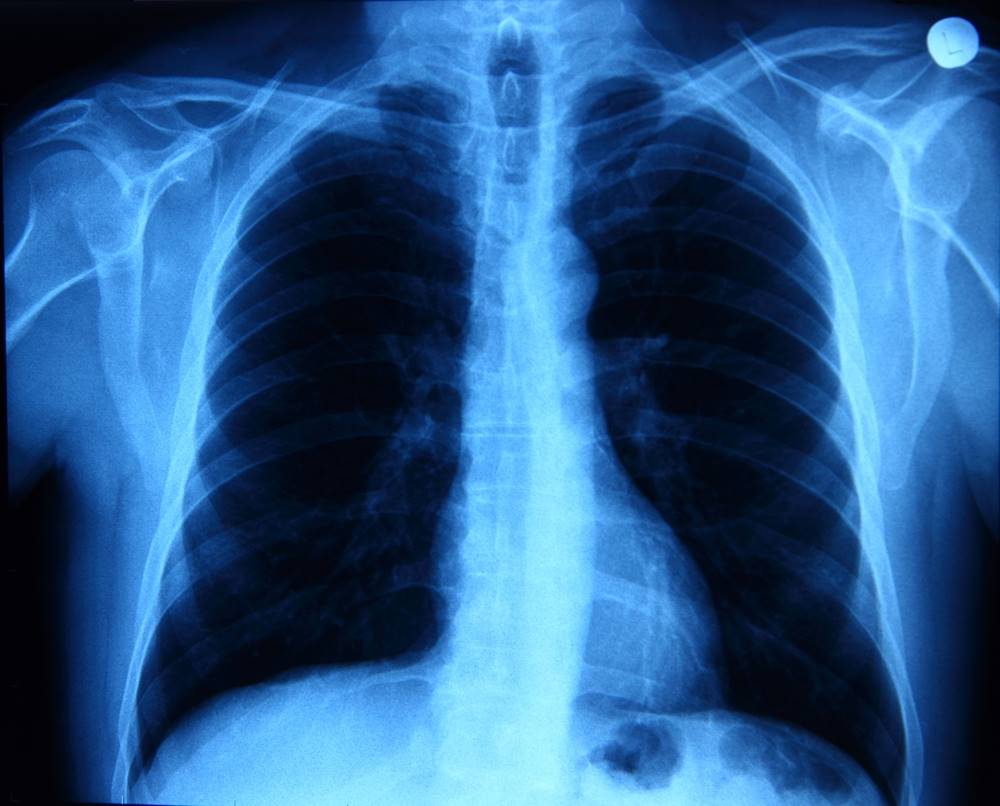

- des pneumonies pouvant provoquer des complications respiratoires,